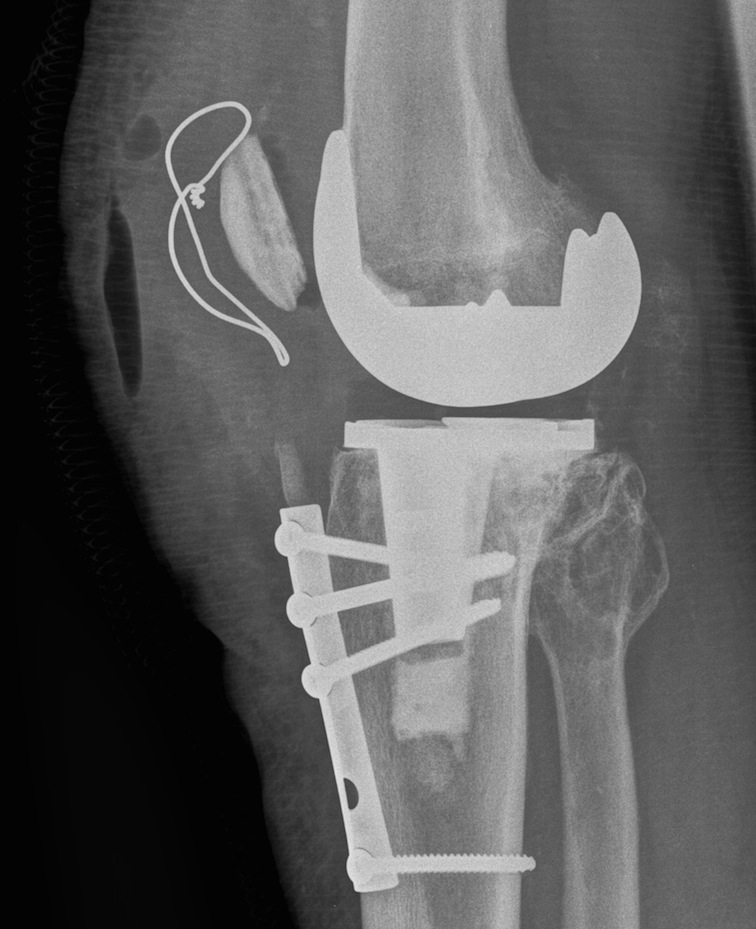

Surgical options

1. Lateral release + Patella resurfacing

2. Tibial tuberosity transfer +/- MPFL reconstruction

Barber et al Arthroscopy 2008

- 91% successul in eliminating instability in 35 knees

- used Elmslie Trillat

3. Revision

Options

- medialise patella component

- revise malrotated components